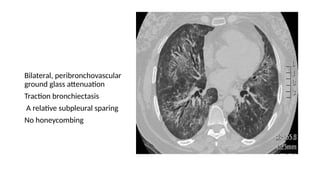

• Computed tomography (CT) features: (A)Axial and (B) coronal CT show confluent bilateral lower

lobe ground glass opacities with marked traction bronchiectasis and

lower lobe volume loss.

• The peribronchovascular predominance with subpleural sparing is well shown on the axial image.

Bilateral, peribronchovascular

ground glass attenuation

Traction bronchiectasis

A relative subpleural sparing

No honeycombing

• Computed tomography(CT) features: (A)Axial and (B) coronal CT show confluent bilateral lower lobe ground glass opacities with marked traction bronchiectasis and lower lobe volume loss. • The peribronchovascular predominance with subpleural sparing is well shown on the axial image.

Bilateral, peribronchovascular ground glassattenuation Traction bronchiectasis A relative subpleural sparing No honeycombing